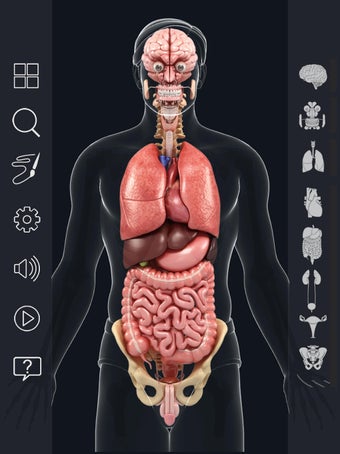

My Organs Anatomy es una aplicación de anatomía 3D gratuita desarrollada por Visual 3D Science para usuarios de Android. Esta aplicación proporciona un modelo 3D altamente realista de los órganos humanos que se puede girar 360°, acercar y alejar, y ver desde cualquier ángulo. La aplicación está diseñada para proporcionar una mirada detallada a la anatomía de los órganos humanos y ofrece varias características para ayudar a los usuarios a explorar y aprender.

La interfaz fácil de usar de My Organs Anatomy permite una navegación sencilla, lo que facilita la selección, rayos X, ocultación y visualización de órganos individuales. La aplicación también incluye un modo de animación, opciones de búsqueda y un panel de información que proporciona información relacionada. Además, la aplicación ofrece pronunciación de audio para todos los términos anatómicos, e incluso los usuarios pueden dibujar o escribir en la pantalla y compartir capturas de pantalla.

En general, My Organs Anatomy es una gran aplicación para estudiantes de medicina y cualquier persona que quiera explorar la anatomía de los órganos humanos en detalle. Con sus gráficos de alta calidad y numerosas características, esta aplicación proporciona una excelente experiencia de aprendizaje para los usuarios.